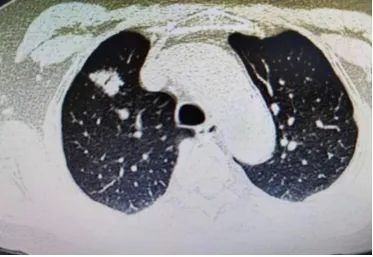

近日,我院外三科胸外团队成功实施胸腔镜下肺段切除手术。患者女性,71岁,因发现右上肺结节入院,胸部CT提示右肺上叶见团块状高密度影,大小约18mm×18mm,呈分叶状,内可见空气支气管征,临近胸膜牵拉。通过CT检查外三科张宁副主任医师考虑患者有恶性肿瘤的可能,建议行胸腔镜手术治疗。但患者术前检查提示肺功能较差,血气分析提示氧分压较低。如行右上肺叶切除,术后有呼吸衰竭的风险,严重影响患者生活质量,综合考虑决定行单孔胸腔镜右上肺前段切除术,尽可能保留患者健康的肺组织。